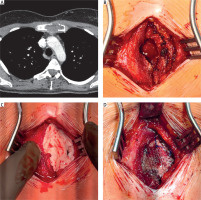

A 31-year-old female patient with suspected aneurysmal bone cyst of the sternum was admitted to the Department of Thoracic Surgery in March 2025 for surgical treatment. The patient was in good general condition, a non-smoker, and without comorbidities. She reported no symptoms. The lesion was incidentally detected during a postpartum spinal MRI performed as a follow-up examination, which revealed abnormalities in the sternum. A chest CT performed approximately 4 months before admission demonstrated an expansile lesion of the manubrium sterni with periosteal disruption and invasion of adjacent soft tissues, measuring 43 × 21 mm (Figure 1 A). The patient was on combined oral contraception containing 0.03 mg ethinylestradiol and 2 mg dienogest, taken once daily. Past medical history included a bone cyst of the left fibula in 2009. Her father had a history of colorectal cancer.

Figure 1

Radiological and intraoperative images. A – Chest computed tomography (CT) scan showing a lesion in the manubrium sterni. B – Intraoperative view of the anterior plate of the sternum with a bone defect. C – Cavity filled with surgical cement mixed with gentamicin. D – Anterior surface of the sternum covered with a mesh fixed with sutures